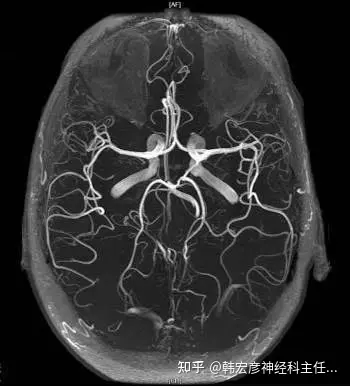

最好的bypass方式是在willis环层次上调整血流:把整个脑血流分为深部供血和皮层供血;如果willis发育好,侧枝发达,完全可以闭塞动脉,不用bypass;如果深部供血可以代偿,但皮层血流不足,可以选择低流量bypass,目的只是补充些皮层血流;如果willis环发育很差,深部供血没有保证,皮层缺血很严重,必须采取高流量bypass,高流量不仅是供血范围,更重要的是压力,这个压力是压力差,首先是缺⾎血严重,压力很低,其次才是高流bypass;很多高流量bypass只是片状的皮层支显影,而未见向willis环的延伸,这样的高流量通常可以被双颞浅动脉动脉bypass取代;现在的MRA与CTA可以观察整个willis环的全貌,与DSA相互补充,可以更合理地选择bypass方式;脑⾎血管bypass的目的不是冒险追求所谓的“治愈”,而是保证安全和血供。